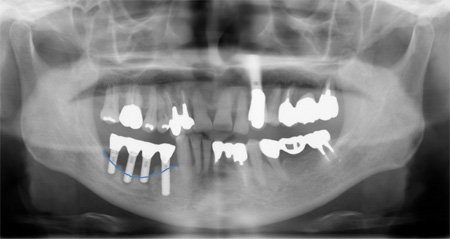

先日歯肉が腫れる、グラグラすると来院された患者さんのレントゲン写真です。 天然歯も重度の歯周炎です。そして向かって左側にインプラント周囲炎がおこり骨がなくなっています。